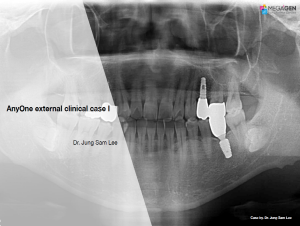

Miguel Stanley, Filipa Calheiros Braga, and Beatriz Mota Jordao, AnyRidge, Immediate Loading, Anterior Maxilla, Scientific background, single replacement